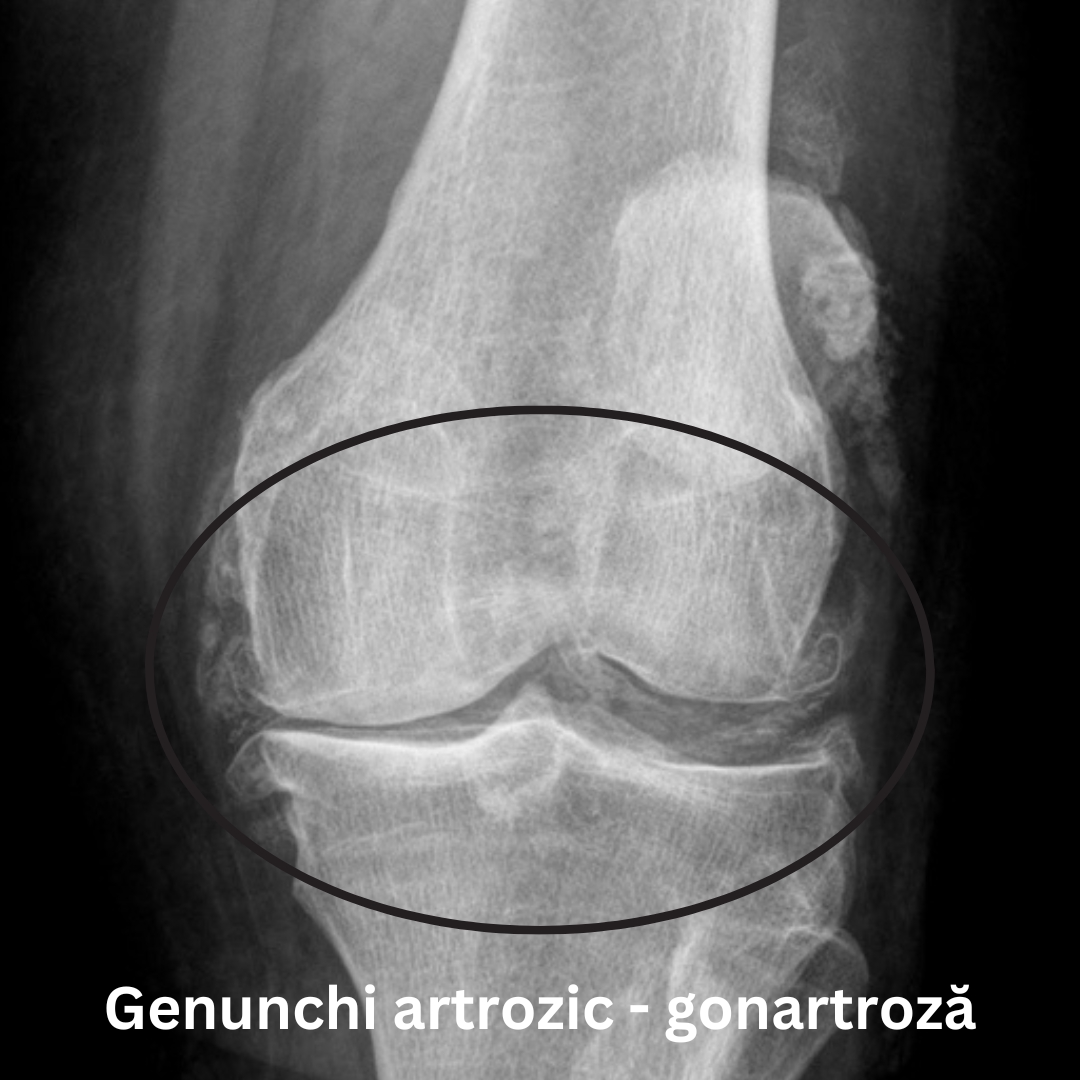

radiografie genunchiradiografie gonartroza

Radiografia unui genunchi artrozic poate arată o îngustare a spațiului articular, modificări ale osului, precum și formarea de osteofite (imaginea din dreapta).